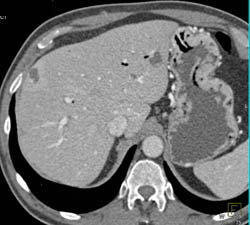

Chronic Pancreatitis